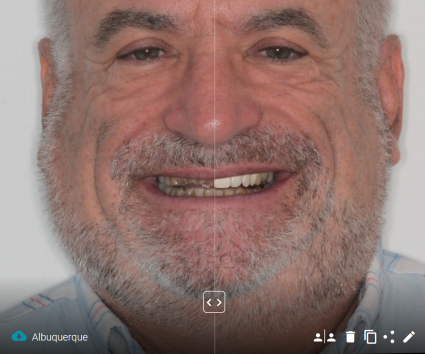

Chaque jour nous sommes confrontés à la nécessité de répondre à l’exigence grandissante de nos patients. Pour y répondre, il nous faut récolter un ensemble d’informations permettant d’établir un état des lieux le plus précis possible. Il faut aussi organiser ces informations avant de les transmettre au laboratoire en même temps que notre projet de traitement.

Pour simplifier cela, il est possible aujourd’hui de créer une sorte de réplique virtuelle de notre patient afin que le praticien et le laboratoire puissent l’étudier, ensuite planifier puis exécuter le travail prévu sans la présence physique de ce patient. Cela est permis par les outils numériques, qui deviennent nos meilleurs alliés dans cette démarche de création d’un « jumeau numérique » après recueil de toutes les données possibles. Ces données peuvent provenir de la photographie, de l’empreinte optique, du CBCT, du « face scan », et aussi maintenant de l’enregistrement des mouvements mandibulaires avec Modjaw. Il n’est pas systématique d’avoir toutes ces données, certaines sont plus indispensables que d’autres, par contre il est important de les centraliser sur une même interface afin de faciliter leur analyse dans le but d’établir un inventaire exhaustif des désordres fonctionnels et esthétiques.

- Présentation d’un cas clinique.

Transformer un cas complexe en cas simple - Explication de la technique des composites injectés